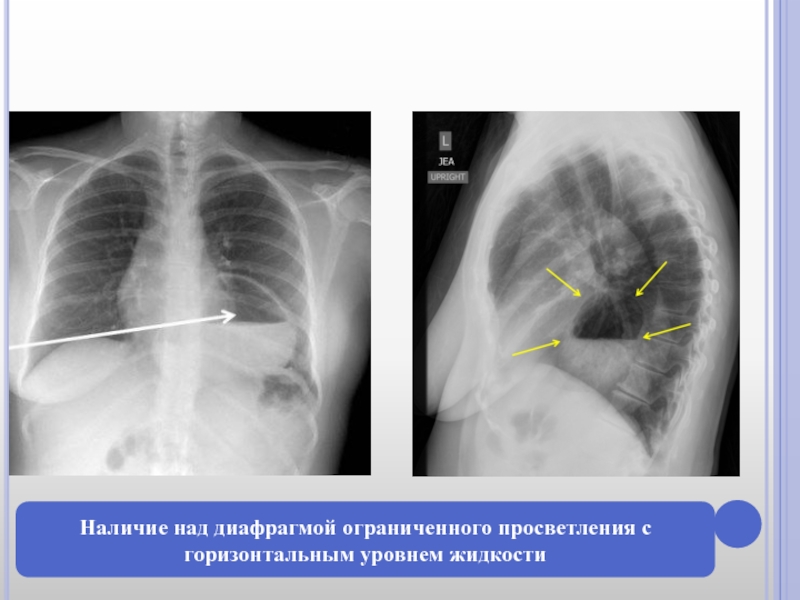

2. Наличие в заднем средостении над диафрагмой ограниченного просветления

с горизонтальным уровнем жидкости или без него, меняющегося по форме и величине в различные фазы дыхания, при натуживании, при компрессии брюшной полости.

Слайд 13Наличие над диафрагмой ограниченного просветления с горизонтальным уровнем жидкости

Наличие над диафрагмой ограниченного просветления с горизонтальным уровнем жидкости